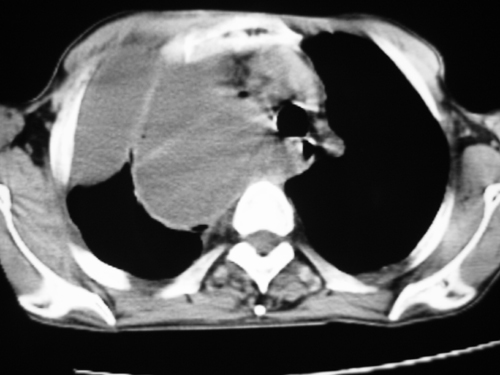

以下是引用zsl6918在2008-4-29 9:15:00的发言:[br]右侧包裹性积液穿刺术后改变,肺内多发结节不除外转移可能。建议查胸水,问病史。